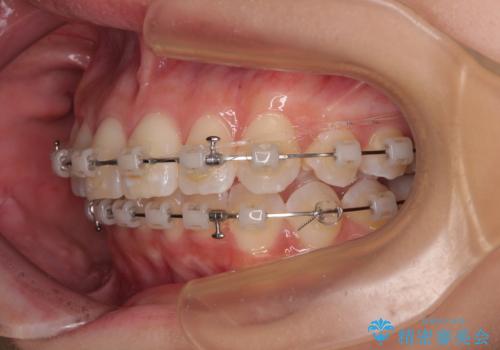

- 審美装置

なかなか舌の突出癖が改善できず、上下前歯が非接触となる期間が長く続きました。

アンカースクリューの活用と、舌のトレーニングを何度も指導し、出っ歯になることなく無事に治療を終えることができました。